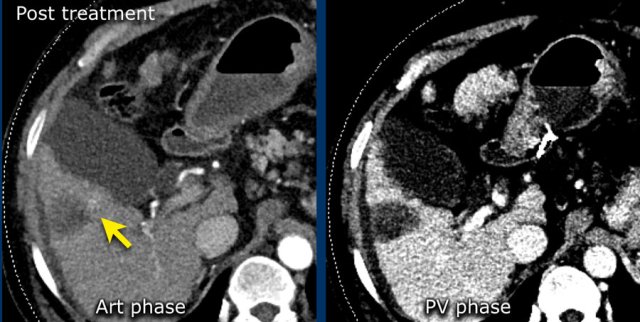

LRTR non-viable

The image in the late arterial phase show normal post treatment pattern with rim-like hyperenhancement of the surrounding liver parenchyma due to hyperemia after DEB-TACE (arrow).

DEB TACE is drug-eluting bead transarterial chemoembolization, a relative new endovascular treatment based on the use of microspheres to release chemotherapeutic agents within a target lesion with controlled pharmacokinetics.

DEB-TACE nowadays represents one of the most used treatments for unresectable hepatocellular carcinoma.